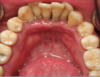

Dental Caries (Figure 10). There is a higher incidence of dental caries seen in those using tobacco products as there is an increased acidity seen in the oral cavity and a decreased buffering capacity of the saliva.8

Figure 10. Dental caries.

Figure 10